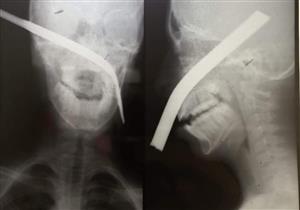

استخراج سيخ من وجه طفل